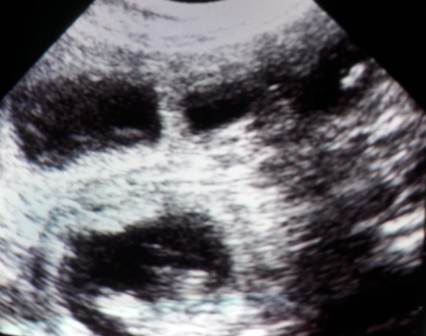

Ich konnte mich nicht zurückhalten und musste heute noch einmal nachsehen :)

Franzi und ich haben viele Fruchtblasen, muntere Babys und schlagende Herzchen gesehen!

Zählen war unmöglich, wie ihr auf dem dritten Bild sehen könnt,

haben sich manchmal an einem Platz fünf Fruchtblasen geöffnet :O

Oft lagen zwei dicht nebeneinander, wie auf dem letzten..

Wir sind sehr gespannt!!!